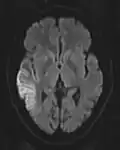

The most common application of conventional DWI (without DTI) is in acute brain ischemia. DWI directly visualizes the ischemic necrosis in cerebral infarction in the form of a cytotoxic edema,[38] appearing as a high DWI signal within minutes of arterial occlusion.[39] With perfusion MRI detecting both the infarcted core and the salvageable penumbra, the latter can be quantified by DWI and perfusion MRI.[40]

-

DWI showing necrosis (shown as brighter) in a cerebral infarction -